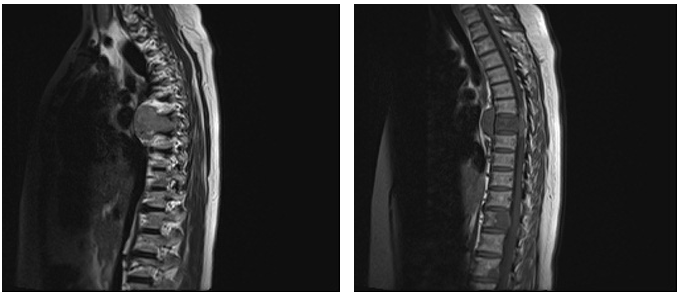

The patient’s lab data was acceptable except a low 25OH Vit D level (10ng/ml). Spinal magnetic resonance imaging (MRI) revealed a mass involving most of the T7 vertebral body (Figure 1);

Figure 1: MRI shows mass involving T7 vertebral body.

associated with a large lobulated paravertebral soft tissue mass mainly in right anterolateral portion. This was extended into epidural space at T7 level & causes local CSF blocks (Figure 2).

Figure 2: MRI shows large lobulated paravertebral mass in right anterolateral T7.